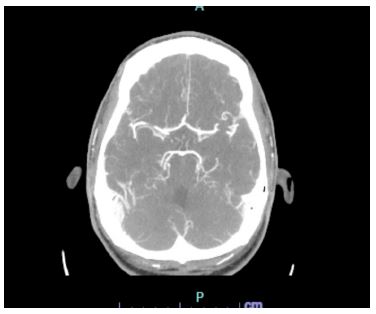

In the ED the patient denied any current symptoms and the physical exam was negative for any acute neurological findings with an NIHSS of 0. The patient’s parents at bedside endorsed dysarthria prior to arriving in the ED. A code stroke was initiated in the ED and a CT Head and CT angiogram were taken, both with unremarkable findings (Figures 1 & 2). Shortly after, the patient experienced another episode of dysarthria lasting for less than five minutes, to which a second code stroke was called and a perfusion CT was taken, showing increased Tmax in the left occipital lobe (Figure 3). Patient was transferred to the ICU for tenecteplase administration and observation with serial neurovascular checks and consults from neurology, cardiology, infectious disease.

Figure 1: CT head.